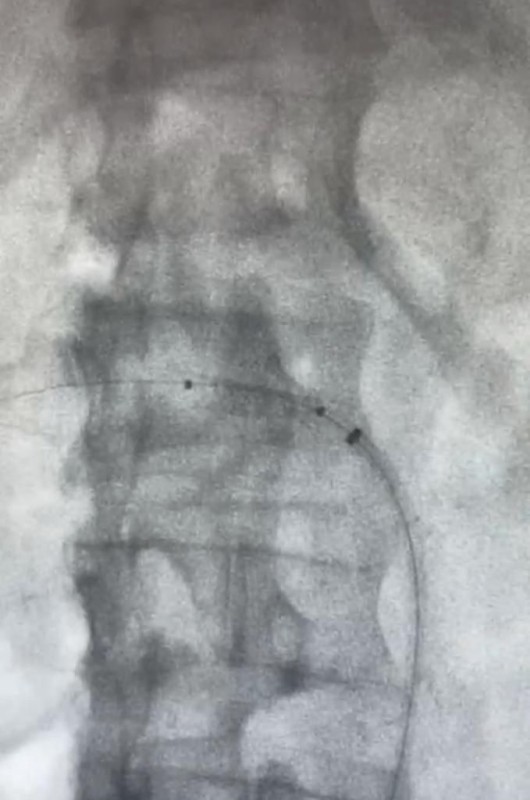

تمكنت فرق طبية متخصصة بالأشعة التداخلية بمستشفى الملك فهد بالمدينة المنورة من تركيب دعامة داخل شريان كلية مريض في العقد السادس من عمره باستخدام ثاني أكسيد الكربون بدلاً من الصبغة.

وأوضح تجمع المدينة المنورة الصحي أن المريض حضر للعيادة وهو يعاني ارتفاع وظائف الكلى وارتفاع ضغط الدم مع وجود صعوبة في التحكم بالضغط، إذ تم عمل التحاليل اللازمة إضافة إلى أشعة دوبلر للأوعية بقسم الدوبلر التي أوضحت وجود تضيق في شريان الكلية اليمنى. وبين التجمع بأنه تمت إحالة المريض إلى قسم الأشعة التداخلية وبعد دراسة الحالة أُجريت للمريض القسطرة، وذلك باستخدام غاز ثاني أكسيد الكربون (بديلاً عن الصبغة) وتم علاج المنطقة المتضيقة بشريان الكلية اليمنى عن طريق وضع دعامة وقد تكللت العملية بالنجاح ولله الحمد. يذكر أن مستشفى الملك فهد بالمدينة المنورة قد أجرى 42441 فحصاً إشعاعياً خلال الربع الثالث من العام الحالي 2022م، فيما أُجريت 1657 عملية جراحية خلال الفترة ذاتها.